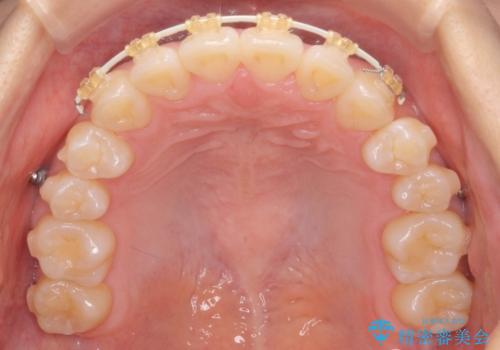

正中のズレ、引っ込んだ前歯の矯正

- 噛んだ時の前歯正中のズレ、引っ込んでいる前歯を治したい。と矯正治療を希望され来院されました。

左上2の前歯はスペースが足りないため、後方に引っ込んでしまっている状態です。

マウスピース矯正システムインビザラインで歯の後方移動、咬合関係の修正を行ったのち、引っ込んでいる左上2をワイヤーを用いて短時間で引き出す治療計画としました。

部分ワイヤー矯正を行なったことで約3ヶ月という短期間で前歯を綺麗に並べることができました。